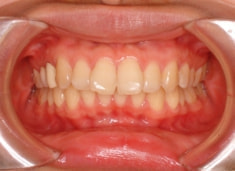

治療前